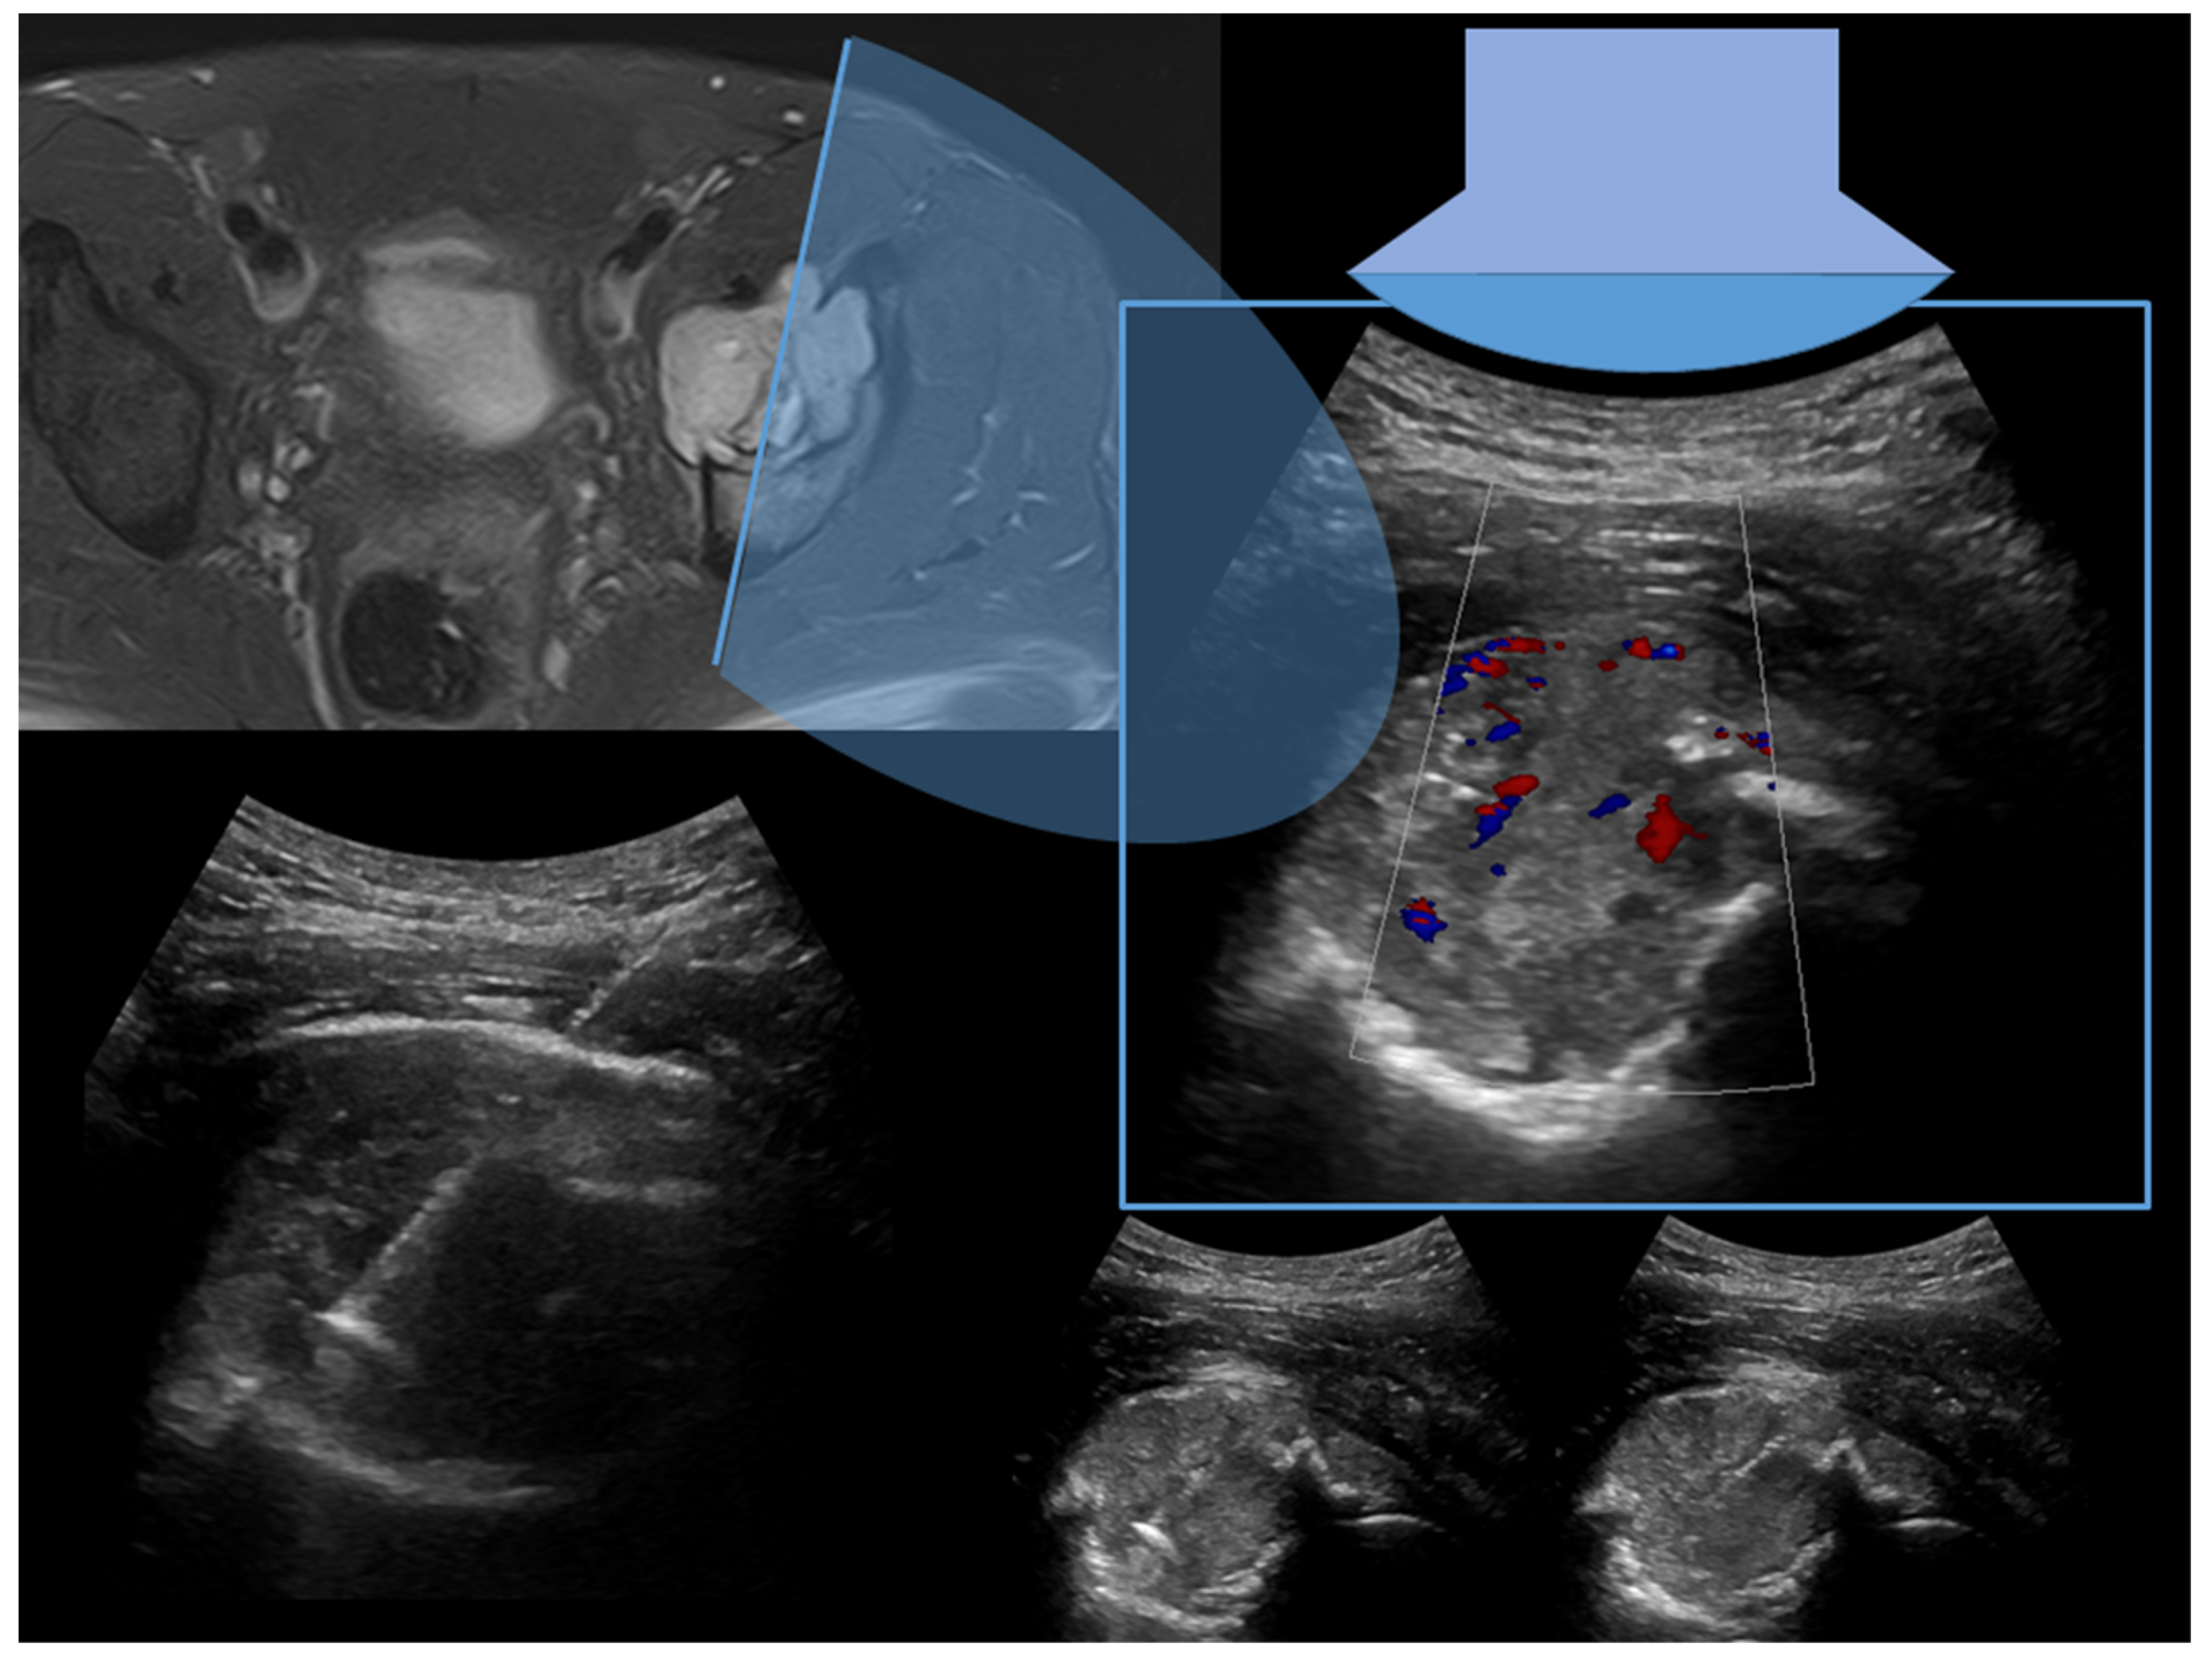

1.1. Percutaneous Bone Biopsy: General Indications

1.2. Imaging Guidance for Percutaneous Bone Biopsy

2. Technical Notes and Overview of Approaches

3.2.4. Target Lesion Location and Hybrid Techniques